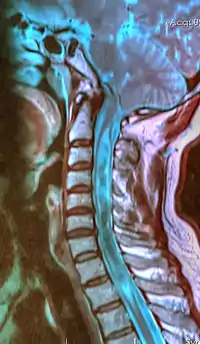

| A sagittal FLAIR MRI scan, from a patient with an Arnold-Chiari malformation, demonstrating tonsillar herniation of 7 mm. | |

Diagnosis is made through a combination of patient history, neurological examination, and medical imaging.[14] Magnetic resonance imaging (MRI) is considered the preferred imaging modality for Chiari malformation.[15] The MRI visualizes neural tissue such as the cerebellar tonsils and spinal cord as well as bone and other soft tissues. CT and CT myelography are other options and were used prior to the advent of MRI, unfortunately the resolution of CT based modalities do not characterize syringomyelia and other neural abnormalities as well.

By convention, the cerebellar tonsil position is measured relative to the basion-opisthion line, using sagittal T1 MRI images or sagittal CT images.[16] The selected cutoff distance for abnormal tonsil position is somewhat arbitrary, as not every person will be symptomatic at a certain amount of tonsil displacement, and the probability of symptoms and syrinx increases with greater displacement; however, greater than 5 mm is the most frequently cited cutoff number, though some consider 3–5 mm to be "borderline,"; pathological signs and syrinx may occur beyond that distance.[16][17][18] One study showed little difference in cerebellar tonsil position between standard recumbent MRI and upright MRI for patients without a history of whiplash injury.[13] Neuroradiological investigation is used to first rule out any intracranial condition that could be responsible for tonsillar herniation. Neuroradiological diagnostics evaluate the severity of crowding of the neural structures within the posterior cranial fossa and their pressure against the foramen magnum. Chiari 1.5 is a term used when both brainstem and tonsillar herniation through the foramen magnum are present.[19]